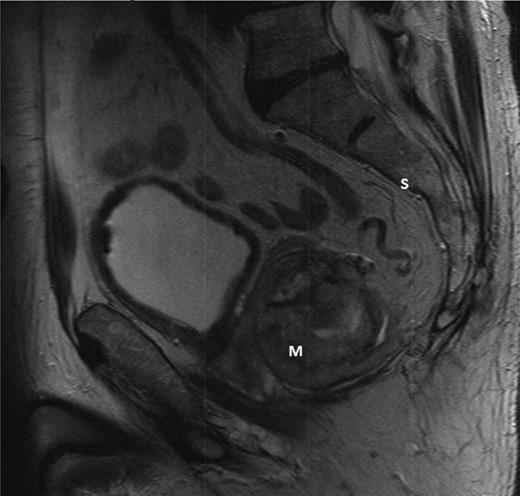

An elderly man in his seventies presented to the Urology department with two episodes of acute urinary retention. There were no rectal symptoms and rectal examination revealed an enlarged prostate. He underwent a laser transurethral resection of prostate during which a large palpable pelvic mass was noted. The subsequent urgent MR pelvis revealed a large tumour in the mesorectum arising from the anterior rectum 10 × 8.5 cm (Figs 1 and 2). A transrectal ultrasound and biopsy were performed; histology revealed a spindle cell tumour, with positive immunostains for CD117 and DOG1 with 5 mitoses per 50 high power fields. This was confirmed to be a locally advanced high-risk GIST.

T2-weighted sagittal image demonstrating a large mass (m) anterior to the sacrum (S) and posterior to the bladder.